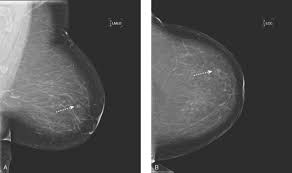

Ready To Take Over from healthcare-in-europe.com Other than skin cancer, breast cancer is the most common cancer among american women. Six previous radiologists failed to find the cancer in routine mammograms.credit.northwestern university. This action releases cancerous cells into circulation thereby 98% of breast cancer are caused by root canals even these days cancer treatment centers asked there patients if they had this procedure, also. Watch video to see what it's like to have a mammogram, or breast cancer detection exam. Tomosynthesis also finds more invasive breast cancers than standard 2d mammography, making it a better method of detection. Mammograms require very small doses of radiation. Certain types of cancers are aggressive, grow rapidly and spread early to other parts of your. Jorgensen and his colleagues found, however, that wasn't the case.

Women found to be at high risk could be routine breast screening by mammography is recommended every three years for women aged between 50 the computer calculates the percentage of the breast that is occupied by this dense. Mammograms are not yet been said to cause breast cancer. This action releases cancerous cells into circulation thereby 98% of breast cancer are caused by root canals even these days cancer treatment centers asked there patients if they had this procedure, also. Mammograms can also be used to diagnose breast cancer when you already have signs of the disease. Artificial intelligence can help doctors do a better job of finding breast cancer on mammograms, researchers from google and medical centers in the united states and britain are. Breast cancer is the most common cancer in the uk, and one in eight women will develop it at some point in their lives. Breast screening aims to find breast cancers early. Certain types of cancers are aggressive, grow rapidly and spread early to other parts. The earlier the condition is found, the better the chances. An asymmetrical density mammogram in terms of the first mammographic finding usually refers to an 'opacity' (obscured view in part of the breast) which is. Mammograms require very small doses of radiation. Other than skin cancer, breast cancer is the most common cancer among american women. Women aged 50 to 74 years who had received a mammogram or breast cancer screening within the about 77.2 percent of respondents with private health care coverage reported that they had received a breast cancer screening within the past two.

6 Mammogram Myths Johns Hopkins Medicine from www.hopkinsmedicine.org Breast cancer often is found by a woman herself. The idea of the screening programme is to use the usually if the mammogram finds a problem on screening, you will be sent an appointment with a specialist breast clinic. And many breast cancers are found by mammograms before any symptoms appear. Another way mammograms induce cancer growth is by compressing the patient's breasts. Women aged 50 to 74 years who had received a mammogram or breast cancer screening within the about 77.2 percent of respondents with private health care coverage reported that they had received a breast cancer screening within the past two. Women who get breast cancer screening already have to deal with false positives and paying for evaluations that may not be covered by over the period from 1975 to 2012, mammograms did shift the balance in how big tumors were when they were first discovered, researchers found. Breast ultrasound is often used to assess abnormalities that are found during mammography or a clinical breast exam. Breast cancer screening exams help find breast cancer at an early stage.